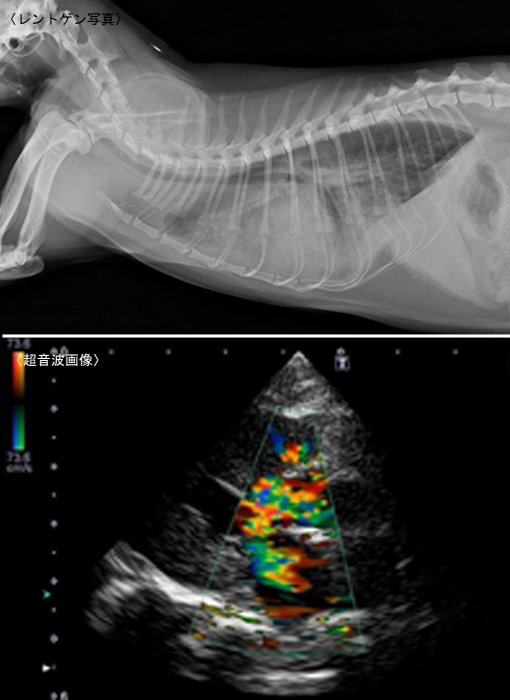

5/31/17レントゲン 心臓の形や肥大していないかなどをみます。 超音波 心臓の血液の流れ、壁の厚さなどの状態をみます。 血液検査 心不全によって起こる肝臓や腎臓の機能の低下や、多血症になっていないかを調べる。 血圧測定 血圧の変化をみる。. 7/13/18胸のレントゲン写真で心臓の大きさを測ってみよう! 18年7月13日 admin 放射線科 最近、死亡原因としてテレビなどでよく耳にする 「心不全」 という言葉がありますが、病名だと思っている方が多いのではないでしょうか? 実は、 「心不全」 という言葉は病気の名前ではなく、心臓のポンプ機能が低下し身体のあらゆるところへと影響が及んだ状態を言います. 犬の心臓病で一番多い病気は僧帽弁閉鎖不全症です。 そして、この地域で特に多く見かけるのはフィラリア症です。 僧帽弁閉鎖不全症は防ぐことができませんが、フィラリアは予防することができます。 猫で多い心臓の病気は心筋症です。 また、猫でもフィラリアにかかると言われています。 これらの病気の診断には、レントゲン、心電図、血液検査、心エコー.

Previous 一覧へ Next ». レントゲン検査 正常な犬の心臓のレントゲン画像です。 僧房弁閉鎖不全症を発症した犬のレントゲン画像です。 心臓の陰影が拡大し、横から撮ったレントゲンでは、心臓によって気管が背側に変位しています。 気管が圧迫されることで咳が出ます。 また、肺の一部が白くなっていて、水が貯まっている状態( 肺水腫 )が示唆されます。 肺水腫では溺れた状態. 犬 心臓肥大、チアノーゼの応急処置は? こんにちは。 今我が家には、今年14歳になるキャバリアがいます。 憎帽弁閉鎖不全症?(心臓肥大)のため、ジゴシン、硝酸イソソルビド、フロセミドというお薬を常 質問No.

5/27/18犬のレントゲン撮影にかかる平均的な費用 犬のレントゲン撮影検査の1回の平均費用は、小型~中型犬で5,000~10,000円、大型~超大型犬で8,000~15,000円となります。 ただし、犬のレントゲン検査を緊急時に夜間救急病院や救急病院にて受ける場合、検査や処置の他に、夜間料金(8,000円~)、緊急対応料金(5,000円~)などの費用が別途かかります。 また緊急時には. 心疾患 動物たちの長寿化に伴い、心疾患の動物たちが増えてきています。 一言で“心疾患”と表現しても、その病態は様々です。 それぞれの心臓に合わせた治療法を実施する必要があります。 心臓の評価は、レントゲン検査、超音波検査、全身状態 (心拍数・呼吸状態・脱水・体重の増減)、血液検査、心電図検査などで行います。. レントゲン検査 左心肥大 心臓エコー検査 右側からの傍胸骨短軸・大動脈レベルにて肺動脈内にモザイクを認める 全収縮期性のプローブに向かう乱流 診断 pda(動脈管開存症) 治療 動脈管結紮術をお.